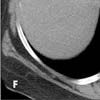

A CT image below the level of the heart (E) shows extensive venous collaterals that extend to the inferior vena cava (arrows). Venous collaterals extending to the inferior vena cava are also evident on another slice in the upper abdomen (F, arrows).

The lesion in the right supraclavicular region is visible on the superior aspect of the study (G, arrow). Images in lung windows, surprisingly, are unrevealing, as are images of the more cephalad aspects of the neck.